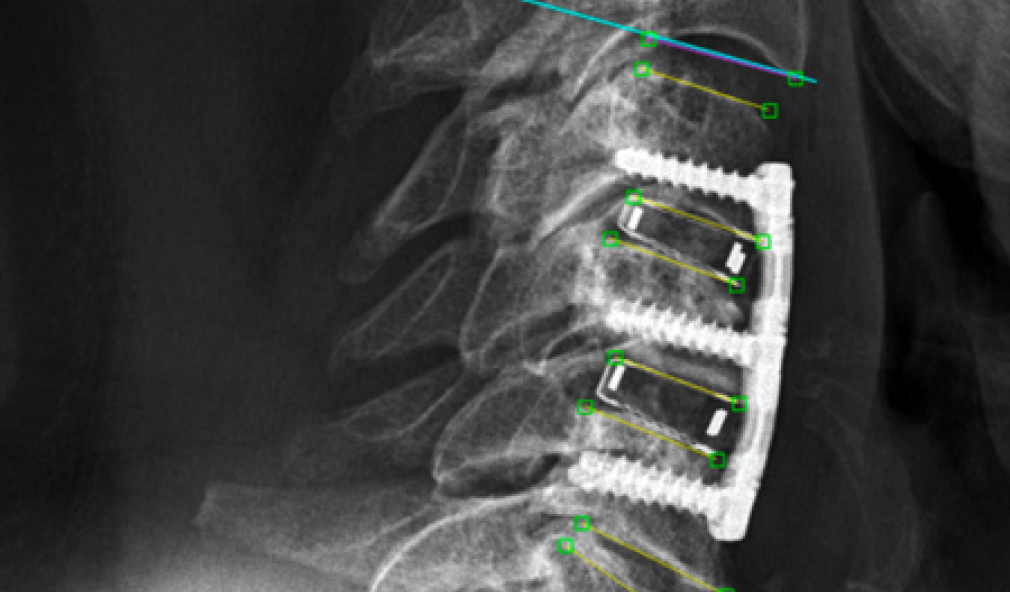

Röntgenbild Wirbelsäule

Une petite correction avec de grands effets sur la colonne vertébrale

Le redressement de la nuque suite à une opération de la colonne vertébrale peut retentir de manière positive sur l’ensemble du rachis cervical. C’est ce que révèle une étude réalisée par notre équipe dédiée à la colonne vertébrale.